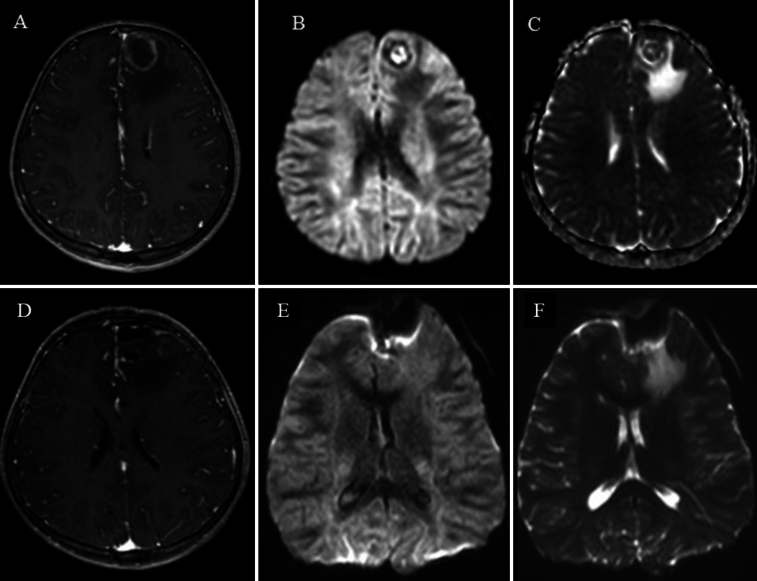

Observations: The authors report the case of a 10-year-old immunocompetent female who presented with absence seizures and vomiting. Brain MRI revealed a left frontal lesion with peripheral contrast enhancement and diffusion restriction, suggestive of a cerebral abscess. She was started on antibiotics and underwent resection. Histopathology confirmed ALK-positive primary CNS ALCL. The patient was treated with NHL-BFM (non-Hodgkin lymphoma-Berlin-Frankfurt-Münster) chemotherapy, the ALK inhibitor lorlatinib, and focal cranial radiotherapy (18 Gy/22 fractions). She remains in complete remission at 18 months. A systematic review of 15 pediatric ALK-positive CNS ALCL cases revealed male predominance, supratentorial location, and inconsistent treatment protocols. Methotrexate-based chemotherapy was most common treatment; the role of radiotherapy and surgery varied.